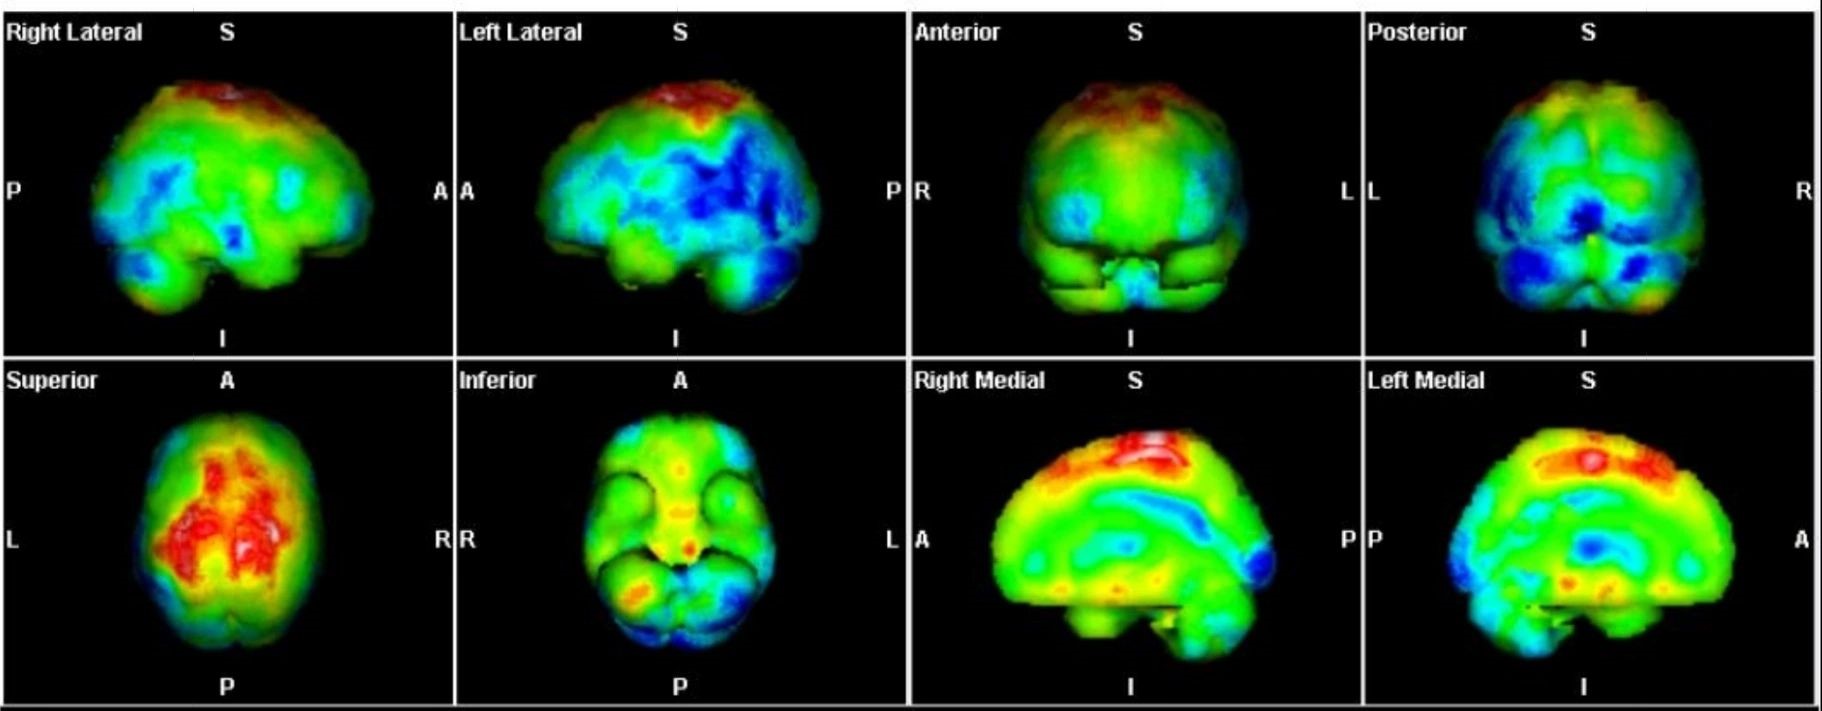

Με τη SPECT‑CT ποσοτικοποίηση υπολογίζουμε απορροφούμενες δόσεις σε όγκους και όργανα‑στόχους (νεφροί, σιελογόνοι, ήπαρ, μυελός κ.ά.). Αυτό:

Σημείωση: Σύμφωνα με πρόσφατες κλινικές εργασίες/σειρές ασθενών – όπως οι LUMEN‑2 (για ΝΕΤ) και νεότερες μελέτες σε PSMA‑στόχο – η ποσοτική δοσιμετρία συσχετίζεται με την έκβαση και βελτιώνει τον θεραπευτικό σχεδιασμό.

Με βάση τα σύγχρονα Guidelines όλων των διεθνών ογκολογικών εταιρειών η μεταθεραπευτική απεικόνιση είναι προαπαιτούμενο για την έναρξη-συνέχιση της θεραπείας και το βέλτιστο αποτέλεσμα αυτής.